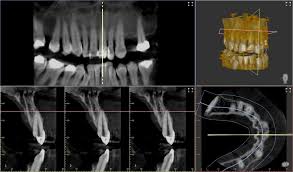

Tu clínica dental, ahora con un servicio de imágenes odontológicas propio

Instalamos equipos de radiología dental dentro de tu clínica, sin que tengas que invertir un peso

Nosotros ponemos los equipos, la habilitación y los costos. Compartimos los ingresos.